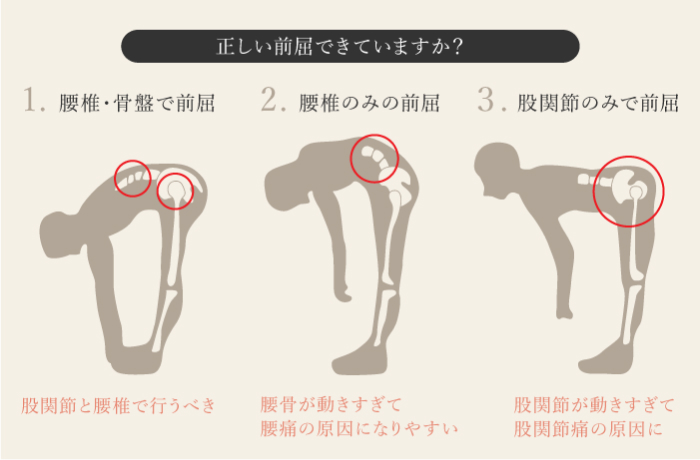

腰を曲げる動作が原因

腰椎が後方にシフトしてしまっているために症状がでます。

腰を反る動作が原因

腰椎が前方にシフトしてしまい椎間関節などに症状がでる。

腰を後ろに反らしたり、仰向けに寝ていると痛みが出ることがある。